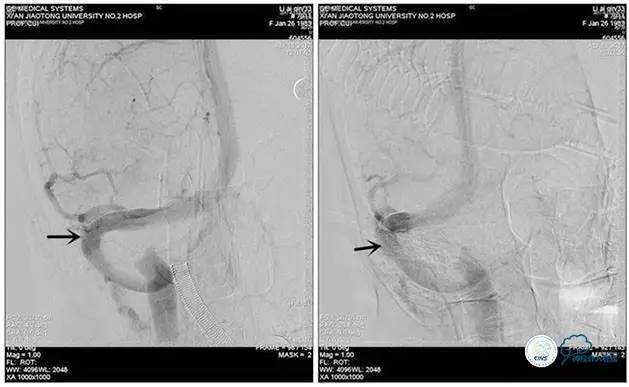

术中测压

远端压力:530mmH2O

近端压力:120mmH2O

术中造影

术后造影

狭窄较前有改善

术中测压:

远端:520mmH2O,

近端:190mmH2O。

治疗方案:

1、8mm×40mm , EverCross球囊扩张;

2、8mm×40mm,Protégé自膨支架成形术。

术后右侧ICA造影

术后远、近端压力差为:0

术后右侧ICA斜位